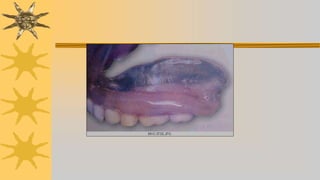

INSTALACION DE LA PROTESIS

Fase final del tratamiento protetico, hay que dedicarle

tiempo suficiente para realizar todos los pasos y tomar las

precauciones necesarias para garantizar el confort del

paciente y que protesis no altere salud gingival

Instalación de prótesis terminada

Examinar dentadura, eliminar de antemano zonas

demaciado retentivas

Eliminar bordes sobreextendidos, su borde debe ser

redondeado no afilado

Eliminar protuberancias internas